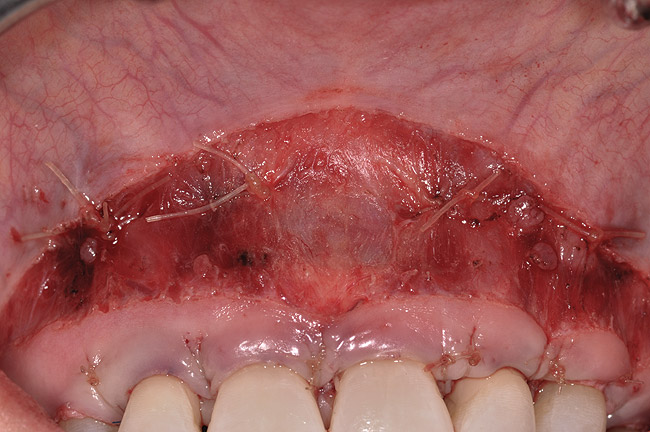

Closure was then accomplished by coronally repositioning the buccal flap and securing the flap using an interrupted sling suturing technique with 5.0 Monocryl™ (Ethicon, www.ethicon.com). The interrupted sling suture technique was started at the mesial aspect of each tooth in the area of the mucogingival junction, and passed interproximally to the distal aspect of the same tooth; the flap was then engaged in the mucogingival junction area, and the suture was passed back interproximally at the distal aspect palatally, then to the buccal from the mesial aspect of the tooth. The suture was then tied off at the mesial aspect. This closure technique was performed for each of the affected tooth sites (Figure 12 and Figure 13).

Once the flap was coronally repositioned and secured, a securing periosteal tac procedure was performed to prevent any micro movement superior to the mucogingival junction in the initial healing phase. A 4.0 chromic gut suture (Surgical Specialties Corp.) was used to engage the periosteum superior to the mucogingival junction and stabilize the tissues superior to the securing suture (Figure 12 and Figure 13). Multiple periosteal tac sutures may be necessary, depending on the size of the surgical field. Postoperatively, the periosteal tac sutures are routinely removed if not totally absorbed at 7 days; the flap sutures are removed at 2 to 3 weeks, and dermal-securing sutures are removed 1 month after surgery. The 1-year post-treatment clinical view shown in Figure 14 depicts the excellent soft-tissue result, band of attached–keratinized tissue present, and excellent color match to the host gingival tissues.

Fig 5. Periosteal securing sutures.

Figure 5